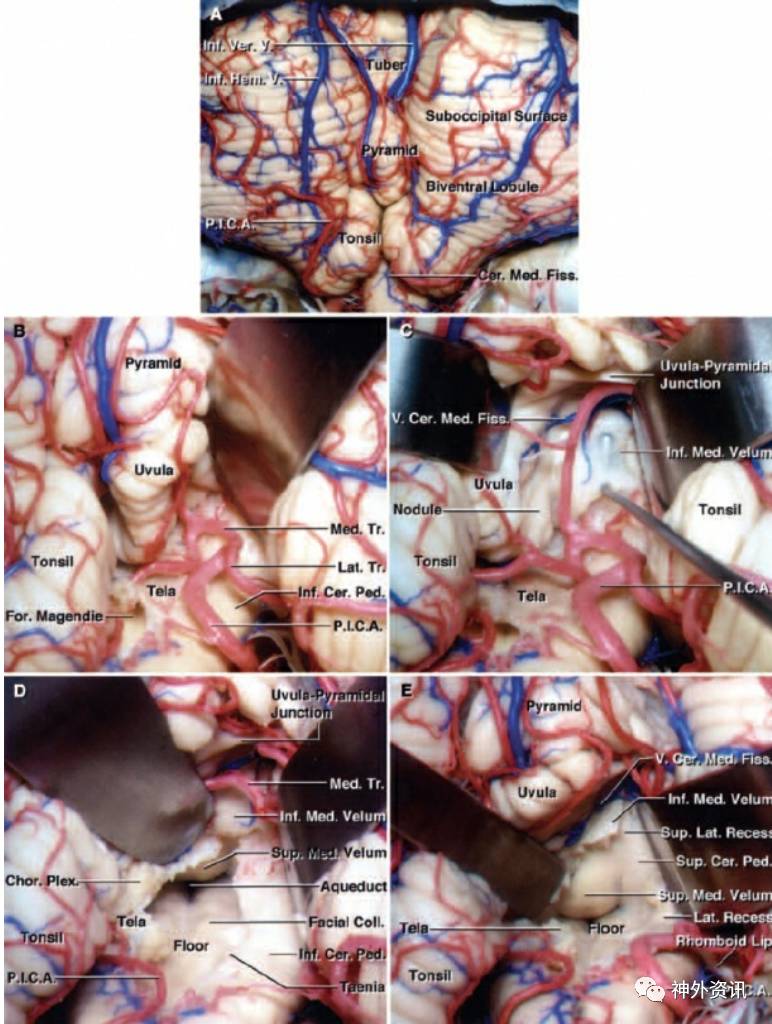

图4. 膜帆入路进入四脑室的基本原则:显露小脑延髓裂和扁桃体蚓垂裂隙(A),通过向外侧牵拉小脑扁桃体显露扁桃体蚓垂间隙。PICA的双分叉被显露后,识别并保护其内侧干和外侧干(B)。牵拉蚓垂显露下髓帆(神经拉钩)(C)。切开脉络膜后,向两个牵开器施加向上的牵拉,打开四脑室。注意向外侧牵开PICA而不牺牲其分支,下髓帆仍保持完整。可见四脑室底和中脑导水管开口(D)。切开同侧的下髓帆可获得上外侧隐窝的显露,可以看见并保护位于小脑延髓裂内的下髓帆嘴侧附近的静脉(E)(图片来自于AL Rhoton, Jr馈赠)。